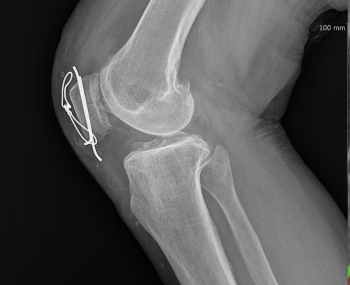

BEFORE AFTER

A+ 3D 골든타임 골절 수술

Before & After